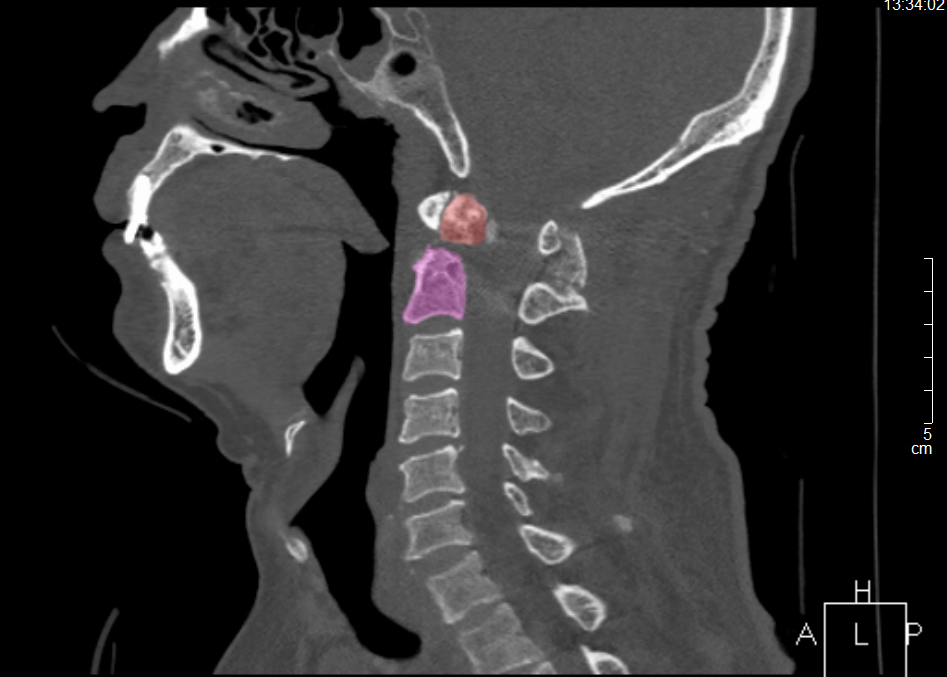

王先生術后CT

8月23日,手術團隊為王先生進行頸后入路寰樞椎復位內固定術+頸椎植骨術,2小時手術順利完成。術后,上頸椎齒狀突陳舊性骨折順利復位,王先生雙上肢酸痛、麻木感基本消失,步態不穩得到明顯改善,困擾了他30余年的疼痛也隨即消失。9月6日,患者康復出院。